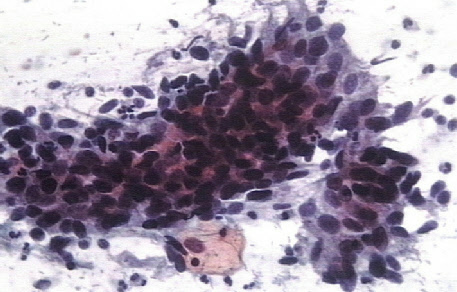

KV-Zulassung der Praxis für gynäkologisch-zytologische Vorsorgeuntersuchungen mit kontinuierlicher, KV-anerkannter Weiterbildung, PAP-Statistik, Stichprobenkontrollen, Recall-System-Angebot an einsendende Praxen.